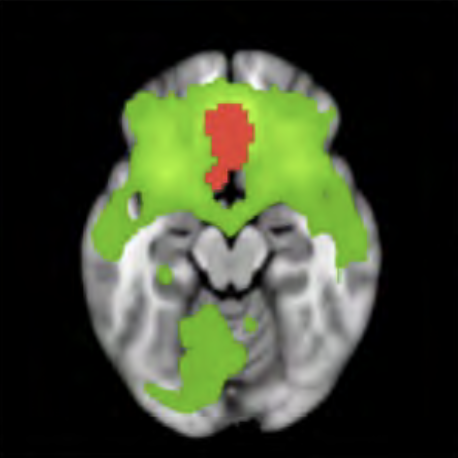

Cerebral Magnetics was developed based in part on the meta-analyses conducted from BrainMap. The BrainMap database allows free access to copyrighted data from imaging studies of 250,000 individuals. The image on the left is an example of a meta-analysis, in this case the analysis displays brain areas involved in speech.